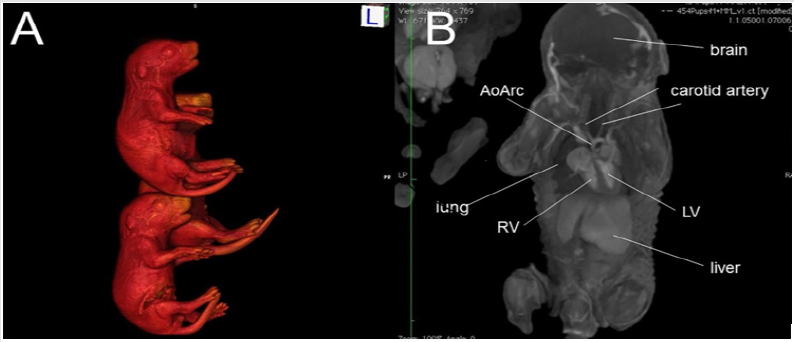

Micro-CT is a powerful imaging modality that utilizes x-ray attenuation to acquire high-resolution three-dimensional images from radio-opaque tissues, such as bones. Iodine-based contrast agents can enhance X-ray attenuation in soft tissues, enabling micro-CT imaging with high accuracy [12,19-21]. Formalin fixed mouse embryos or newborn pups stained with iodine (Figure 1A) by simple immersion in 0.025 N potassium tri-iodide (Lugol) solution can provide excellent contrast, enabling micro-CT scans to be used for performing virtual necropsies [22-24]. A typical scan takes approximately 25 minutes, during which four to eight fixed embryos (embryonic day 12-16) or 12 fixed newborn mouse pups can be scanned at a resolution of 15μm or 45μm, respectively. The imaging data collected in this manner (Figure 1B) can provide remarkably accurate visualization of fetal and newborn mouse anatomy [12,18,19,25]. With the ability to simultaneously image 8-12 fetuses/pups per scan, mutant mice can be readily identified from an entire litter with just a single scan, greatly accelerating the diagnosis of CHD and other structural birth defects.

Figure 1: An example of ex vivo 3D micro-CT of formalin-fixed mouse pups imaged at 46 m X 46 m X 46 m spatial resolution. (A) 3D surface rendering of iodine-stained mouse pups, and (B) a plane from the multi-planar 3D imaging data stack. Abbreviations: AoArc: aortic arch; LV: left ventricles; RV: right ventricle.